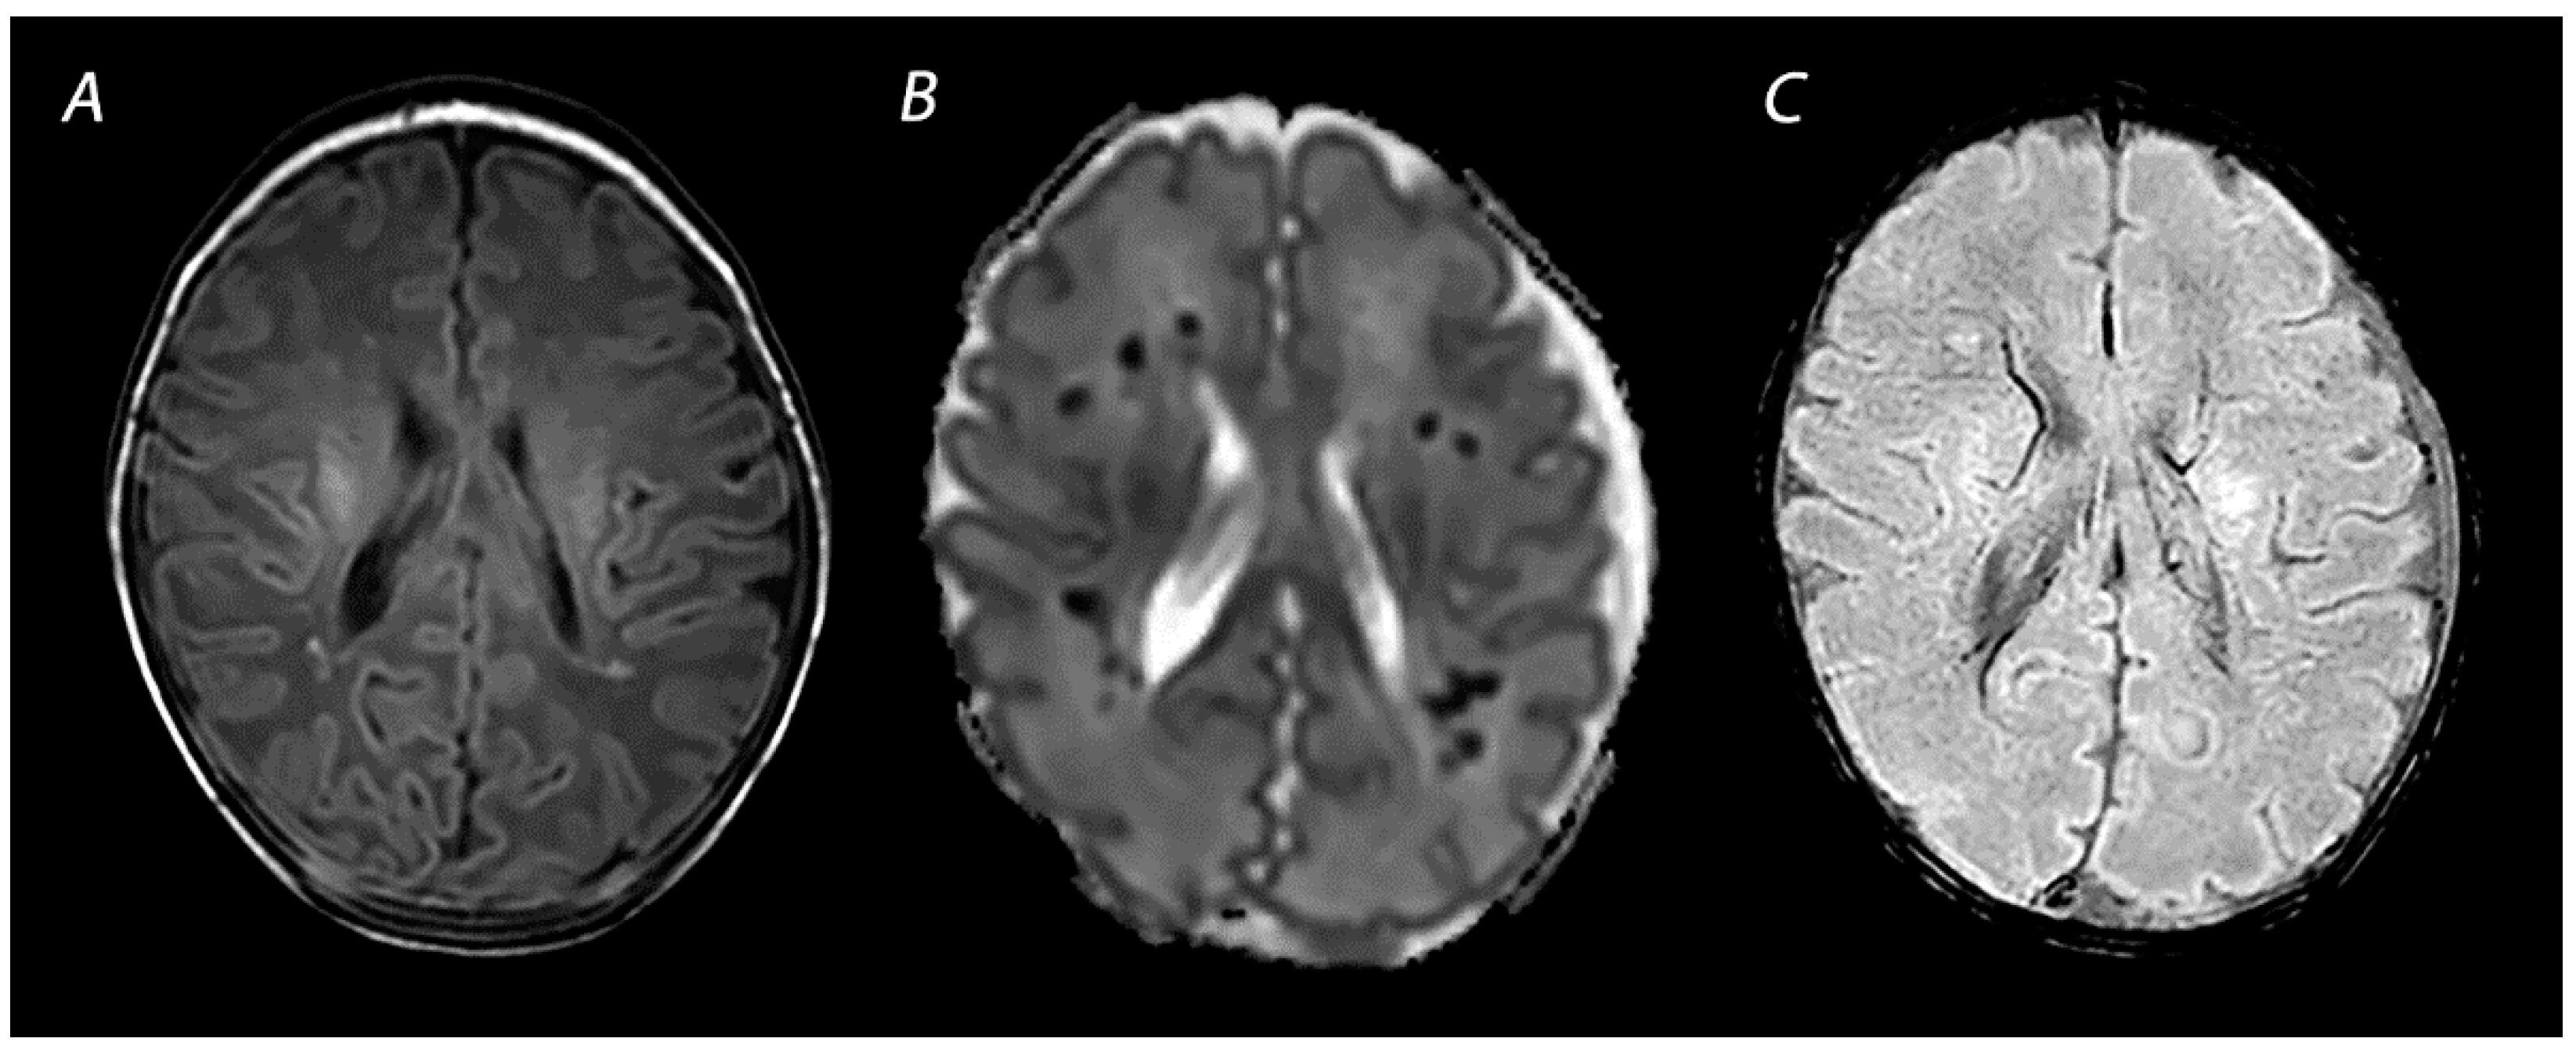

3.2. Diffusion Weighted Imaging

3.3. Susceptibility Weighted Imaging

4. Advanced Imaging Modalities

| SWI | Prominent hypo-intense veins, low signal intensity at the site of hemorrhagic lesions. | Prominent hypo-intense veins have been observed as early as 18 h after birth, but current literature is limited. Low signal intensity at the site of hemorrhagic lesions is seen immediately and can persists for many months. | |

| BGT | T1WI/T2WI | Abnormal signal intensity in the basal ganglia, thalami and the perirolandic cortex. Absence of a normal high-signal intensity of the PLIC. | Inconspicuous or subtle abnormalities in the first days, which become gradually more apparent by the latter half of the first week following the insult. MRI obtained beyond 1 month can show volume loss, cysts, gliosis and impaired myelination of the central gray matter and perirolandic cortex. |

| DWI | High signal intensity on isotropic DWI with low ADC values in affected areas. | Abnormalities peak at 3–5 days after the insult. Pseudo-normalization occurs after approximately 11–12 days for infants treated with therapeutic hypothermia, and 6–8 days in non-cooled infants. | |